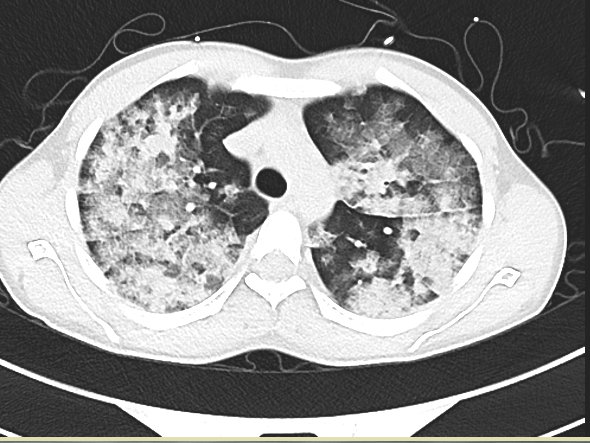

接诊医生在对小辉完善系列检查后发现:小辉血氧饱和波动仅有49%至60%(在不吸氧的条件下,正常血氧饱和度为95%以上),血压为89/63毫米汞柱(血压单位),脉率达每分钟144次,呼吸每分钟39次,双肺满布大量湿啰音,情况危急,随时会有生命危险。接诊医生立即联系了心血管内科,将小辉送至心血管内科接受紧急救治。

大附院心血管内科医师凭着丰富的临床经验,考虑小辉患的是急性肺水肿中极严重的急性高原肺水肿。小辉的病情随时有迅速恶化的风险,一旦得不到有效的救治,小辉即将面临昏迷甚至死亡!他们当即为小辉施行了系列紧急治疗。经过心血管内科医护人员齐心协力的救治后,小辉生命体征逐渐平稳,氧饱恢复到95%。